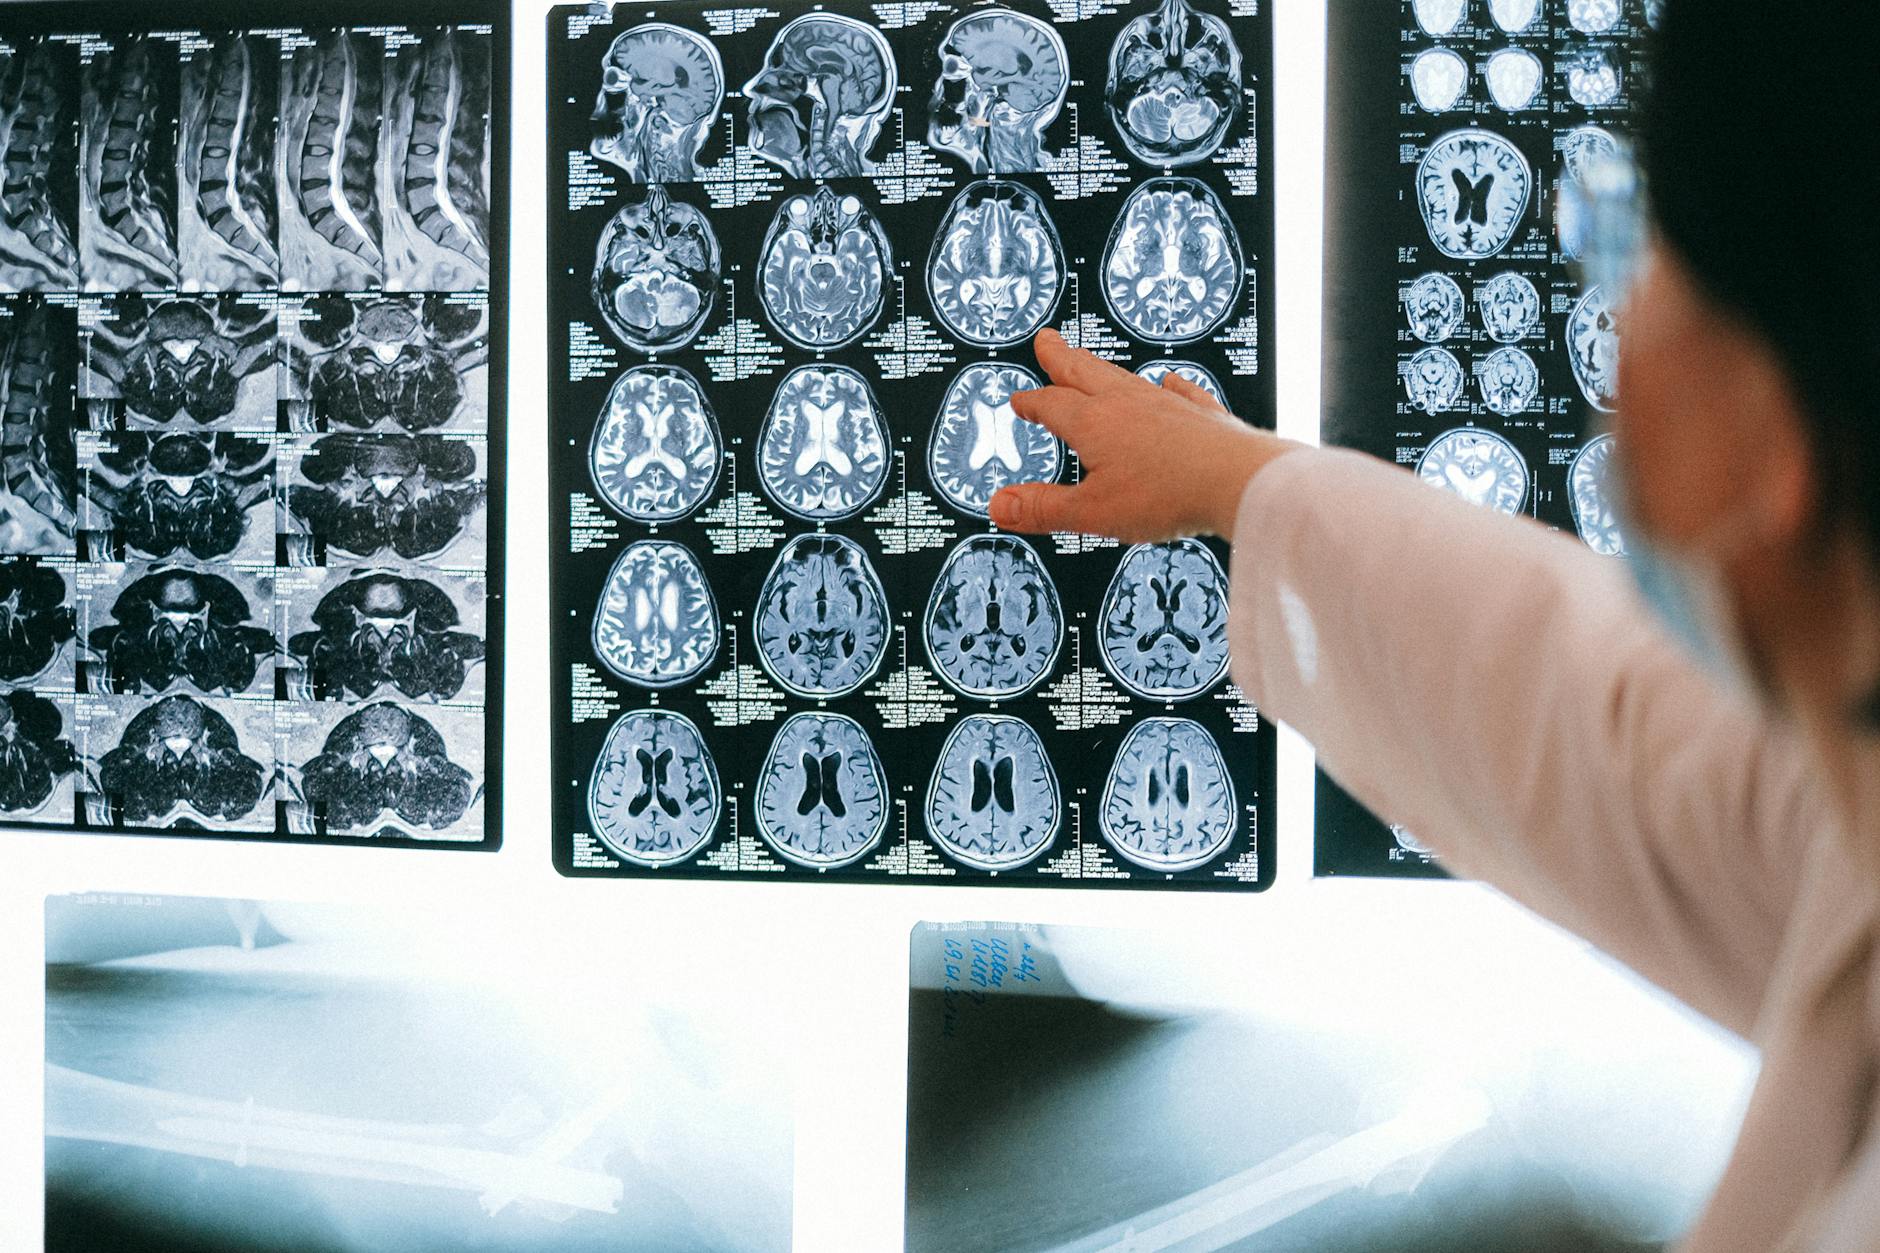

Radyoloji raporu, tanı ve tedavinin temelini oluşturan kritik bir tıbbi görüştür. Son yıllarda yüksek hacimli raporlama modellerinde, raporun kim tarafından ve hangi sorumlulukla yazıldığı hasta açısından çoğu zaman belirsiz kalabilmektedir.

İmzasız ya da kişisel sorumluluğu net olmayan raporlar; hız sağlar ancak güven duygusunu zayıflatır. Oysa hastaların gerçek ihtiyacı, görüntülerinin yeterli zaman ayrılarak incelendiğini bilmek ve gerektiğinde sorularını yöneltebilecekleri bir hekimin varlığından emin olmaktır.

Bil‑Rad'da her rapor, adı ve sorumluluğu açık bir hekim tarafından hazırlanır. Amaç daha hızlı değil; daha güvenilir, daha sahiplenilmiş bir tıbbi değerlendirme sunmaktır.

Bilrad olarak, radyoloji alanında çığ gibi büyüyen kaliteli raporlama talebinin farkındayız. Günümüzde radyolojik tetkiklerin çekim aşamasından çok kaliteli raporlamalarda yaşanan sıkıntıların çözümü için buradayız. Eksik, hatalı, yüzeysel raporlamaların klinisyen hekimleri medikolegal ve etik sorunlarla karşı karşıya bıraktığını biliyoruz. Radyolojik takip ve karşılaştırmalı raporlamalarda çözümler sunuyoruz.